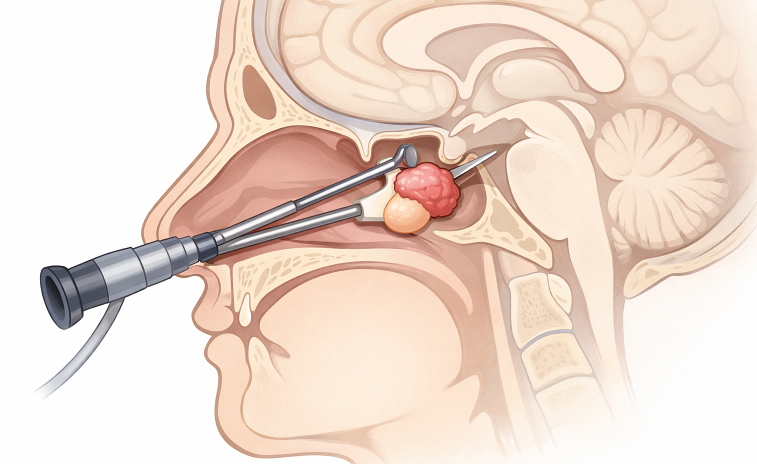

Tratament chirurgical:

Este indicat mai ales în cazul macroadenomelor hipofizare compresive pe nervii optici sau al adenoamelor secretoare nerefractare la tratament medicamentos.

Abordul uzual este cel endoscopic transsfenoidal (prin nas și sinusul sfenoidal) – minim invaziv, eficient și cu risc redus, prin acre se pot aborda cu succes peste 95% din cazuri. Este util mai ales pentru tumorile mici, strict intraselare (microadenoame sau macroadenoame) și are limite în cazul tumorilor mari, extinse supraselar anterior sau lateral, dincolo de planul aretrelor carotide.